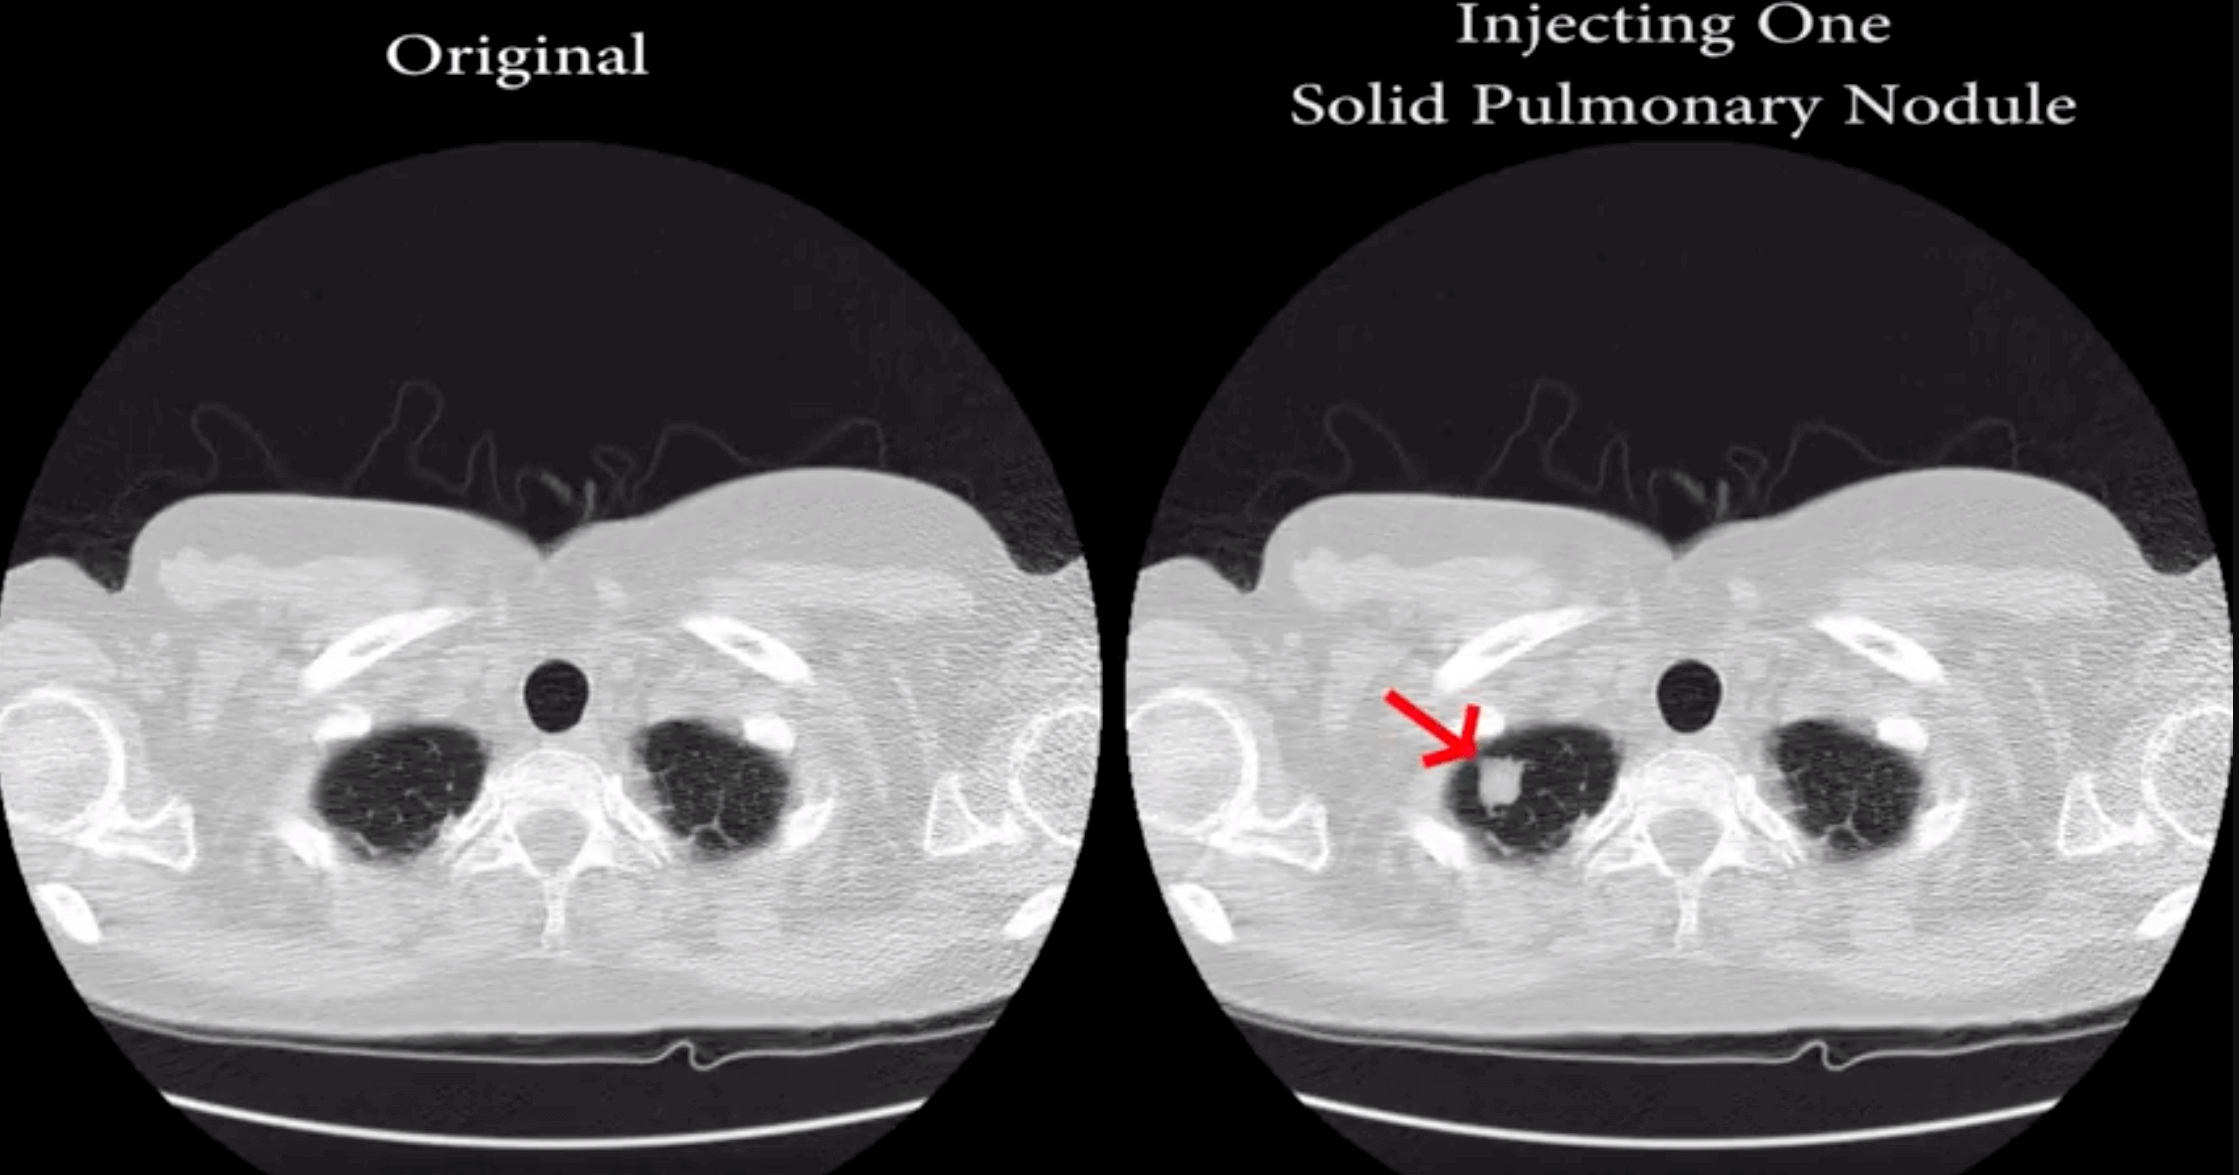

Israeli researchers created malware that can alter CT and MRI scans well enough to fool radiologists into misdiagnosis. The deep-learning software can create realistic looking fake malignant tumors or can hide real growths from scans in close to real time.

"We implement the attack using a 3D conditional GAN and show how the framework (CT-GAN) can be automated," said Yisroel Mirsky, Tom Mahler, Ilan Shelef, and Yuval Elovici in their study. "Although the body is complex and 3D medical scans are very large, CT-GAN achieves realistic results which can be executed in milliseconds. "

In a blind study, using 70 altered lung scans and three experienced radiologists, the software tricked them almost every time. In instances where they were looking at faked growths, they delivered a cancer diagnosis 99 percent of the time. In scans where the malware had removed actual tumors, the radiologist gave the all clear 94 percent of the time.

The radiologists were told that they had been tricked and were given a second chance with 20 more scans with half being altered. They were wrong 60 percent of the time with injected nodules and 87 percent of the time with removed growths.

The researchers then ran tests against software designed to detect lung cancer in images, which radiologist use to confirm their own diagnosis. It misdiagnosed faked nodules 100 percent of the time.